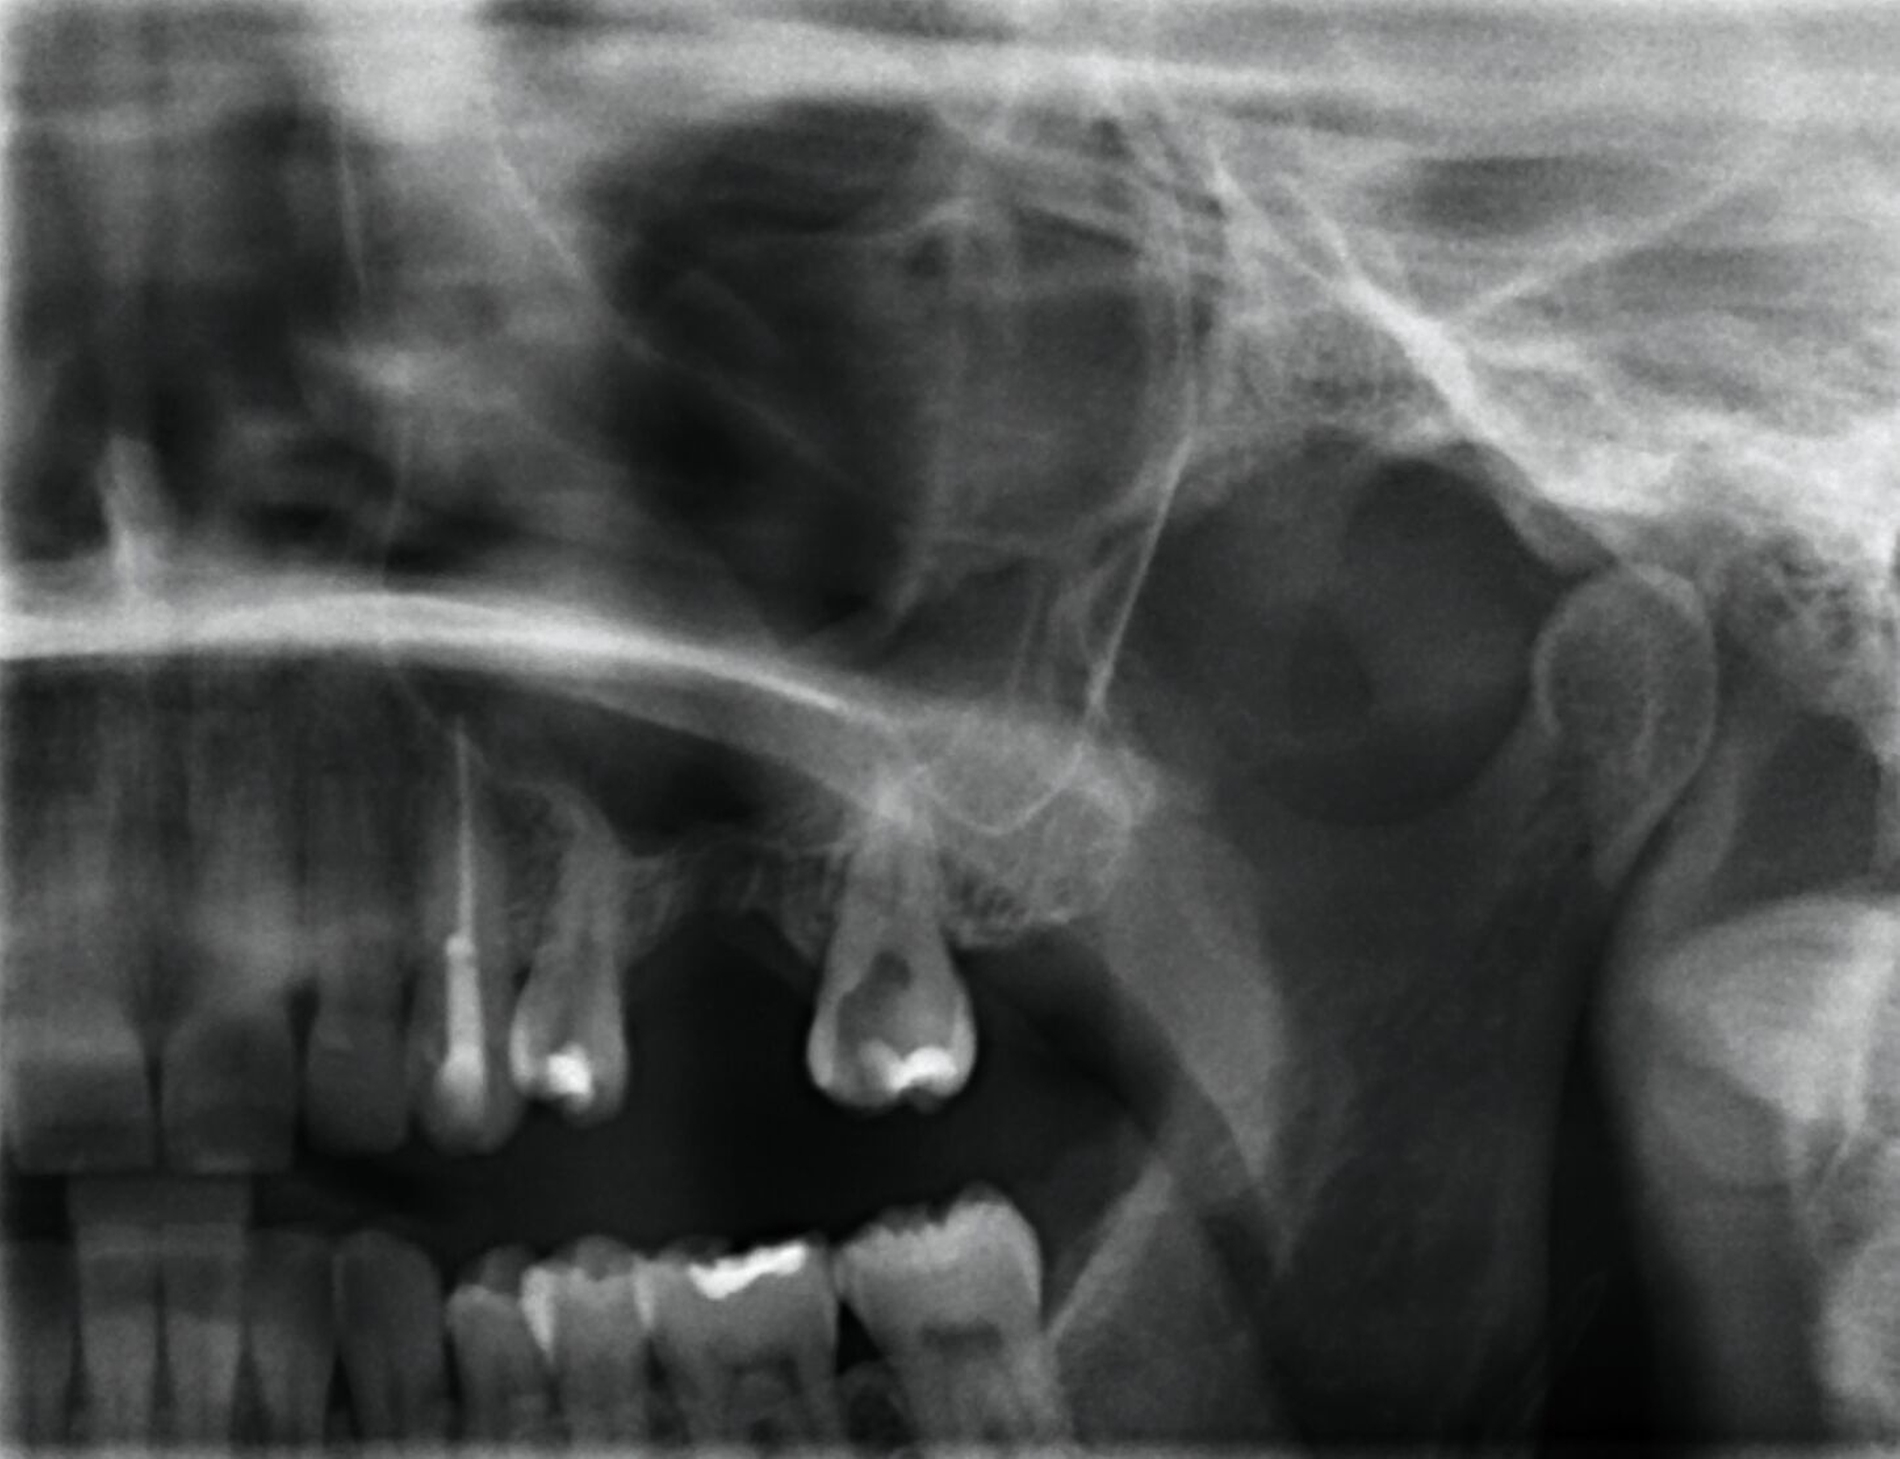

Eine 35-jährige Patientin stellte sich immer wieder mit rezidivierenden Schmerzen der linken Gesichtshälfte bei mehreren Ärzten vor. Die Beschwerden bestanden seit Jahren. Schon im Vorfeld waren mehrfach bei chronischer Sinusitis eine Kieferhöhlenrevision sowie eine Infundibulotomie linksseitig erfolgt. Regelmäßig kam es zu erneuten eitrigen Entzündungen. Die fraglichen Fokuszähne des zweiten Quadranten 24–27 waren vor einigen Jahren entfernt worden (Abbildung 1). 2017 war eine komplikationslose implantologisch-prothetische Versorgung der Freiendsituation erfolgt (Abbildungen 2 und 3).